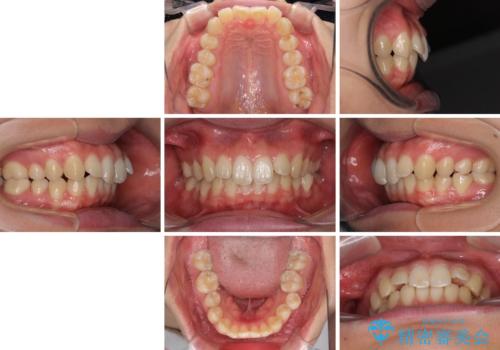

- 上の前歯が下唇に引っかかる感じが気にして来院された患者様です。

上下歯列の前後位置を見ると、上顎が全体的に前方に位置しており、上顎前歯が前方に突出しているものの、横顔の印象はそれほど口元が突出しているものではない状態でした。

口元を極端に引っ込めた印象にしないため、上顎は左右第一小臼歯2本を、下顎は左右第二小臼歯2本を抜歯し、ワイヤー装置にて矯正治療を行うこととしました。